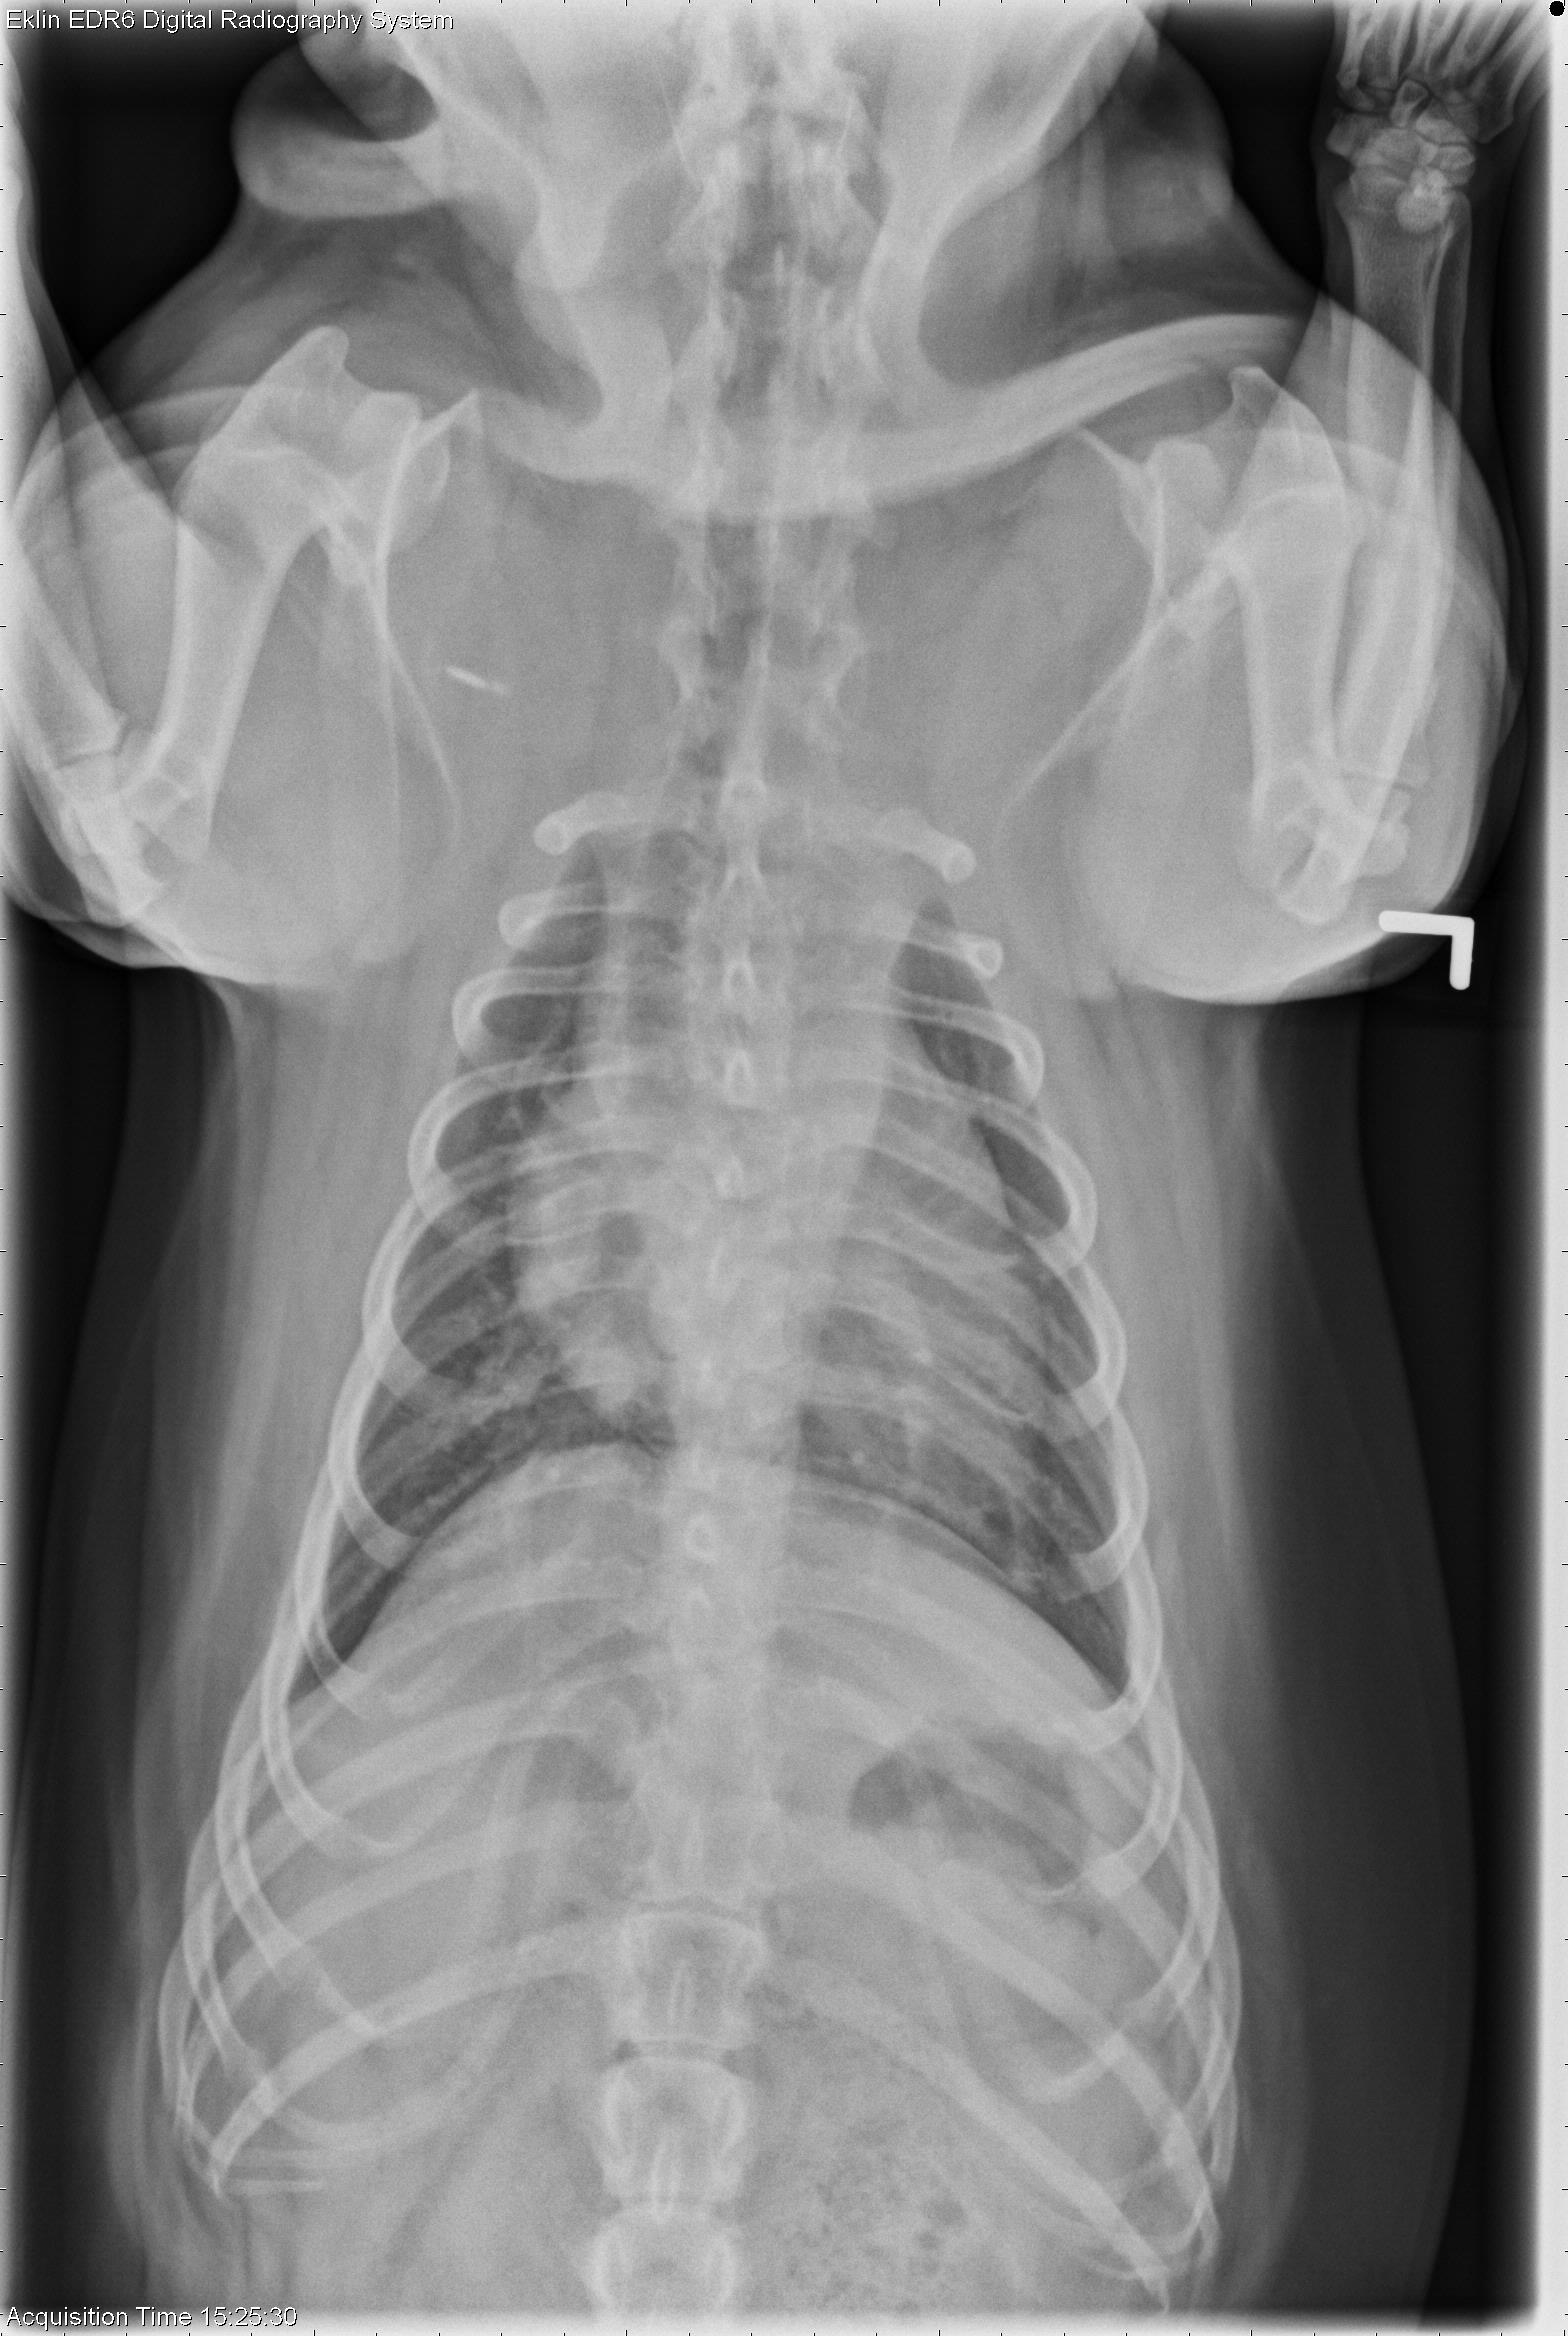

This week’s case is a 2-year-old male neutered French bulldog with central nervous system signs. These radiographs were taken prior to anesthesia.

The cardiovascular structures are normal in size and shape. The airways are patent. There is a broad-based soft tissue and gas opacity at the level of the diaphragm on the left lateral projection. The pleura and mediastinum are normal. Hemivertebrae are present in the thoracic spine, consistent with breed.

The intermittent soft tissue opacity in the region of the esophagus is most consistent with a sliding hiatal hernia, seen commonly in brachycephalic breeds.

• Sliding hiatal hernia (incidental, unlikely related to clinical signs)

• Inflammatory brain disease diagnosed on MRI